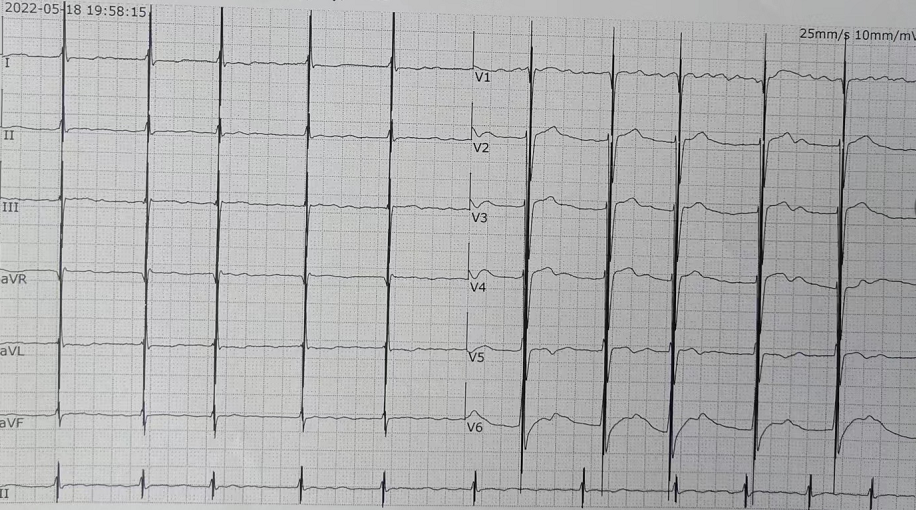

入院检查:甲状腺功能、凝血功能、血常规、hs-CRP均正常范围,eGFR 71ml/min/1.73㎡,BNP 3881.7pg/ml ,肝功能“TBIL 41.2umol/L DBIL 17.1 umol/L IBIL 24.1umol/L”;心电图提示“异位心律,心房颤动,偶发室早,QRS 波宽度113ms”;心超提示“扩张型心肌病 ,全心扩大(左房内径 64mm,左心室舒张末期内径82.1mm),左室壁运动弥漫性减低,二尖瓣中度反流,三尖瓣轻度反流,主动脉瓣轻-中度反流,心律失常,左室收缩功能减低(LVEF 37%)”;心肌MR提示“扩张型心肌病,全心扩大,LVEF 22.4%,左心室基底段-中央段间隔壁心肌中层见点、线样延迟强化”;动态心电图“心房颤动24小时总心搏114767次,平均90次/分,最慢67次/分,最快164次/分,多源室早(1918次,包括单发室早1854次,成对28对,短阵室速2阵)”。

入院时心电图

术后心电图可见CCM脉冲发放,正常运行

3、CCM联合ICD一站式手术的难点:精准的放置三根导线对此次手术尤为关键,也是手术的难点,不仅要求导线参数满足要求,还需要兼顾三根导线放置的位置和间距。首先是准备静脉通路,在右侧锁骨下静脉穿刺,送入导丝,在透视下确认钢丝成功进入右心系统;之后进行囊袋制作;随后进行起搏导线植入,两根起搏导线之间的距离在2cm以上,ICD导线与普通导线距离3cm以上(ICD导线除颤线圈长度,可作为导线之间距离的参考),从而保证CCM的正常感知与发送且不会互相干扰,最终所有电极导线都被精准完成植入,分别测试三根电极导线的起搏阈值和起搏阻抗并记录。连接导线与脉冲发生器,设定输出为7.5V。联合测试,三根电极均可以正常工作且彼此无干扰。同时考虑到除颤的效果,将ICD放置在左侧,CCM放置在右侧。此患者术后心电图对比,完美展示了自身心律与起搏心率下CCM正常工作。